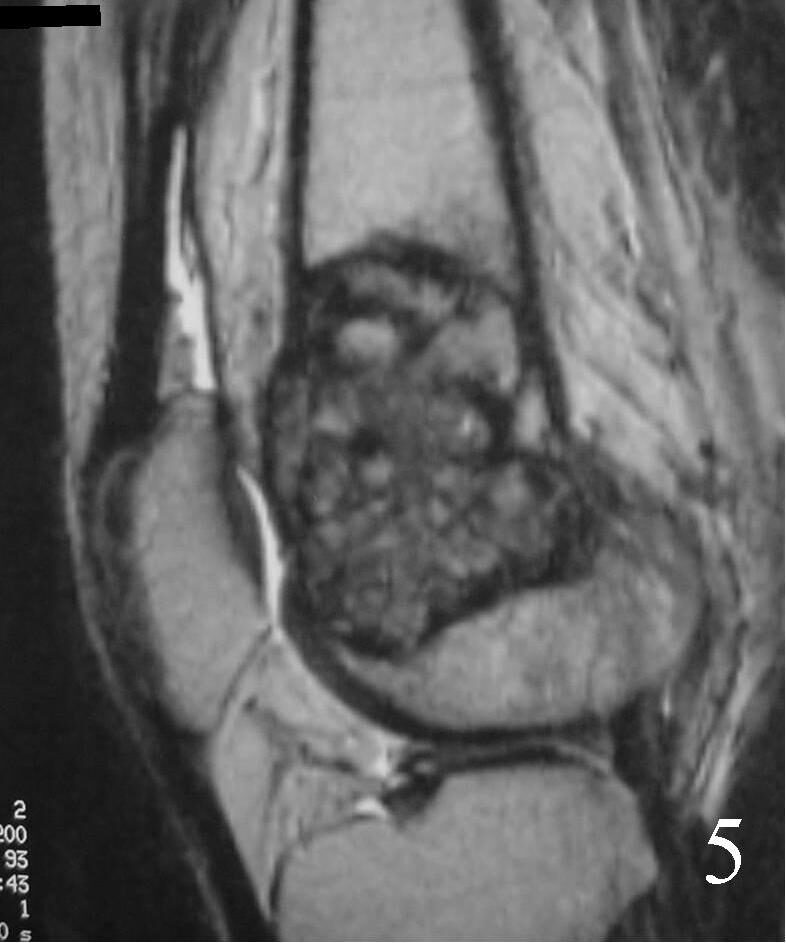

- They will be low to intermediate on T1-weighted images, and intermediate to high on T2-weighted images (Fig. 4, 5, 6)

Fig. 5 Sagittal T1 MRI shows the soft tissue extension anteriorly.